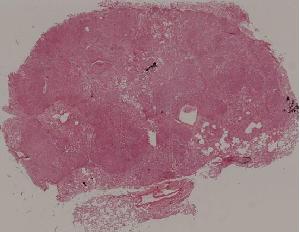

76. Acute pyelonephritis

77. Chronic pyelonephritis

41. Opportunistic infection in the lung

71. Acute transplant rejection of kidney

72. Lupus nephritis

36. Lymphoma

80. Invasive ductal cancer of the breast

84.Graves disease

93. Epidemic cerebrospinal meningitis

94. Encephalitis type B

88. Chronic cavitary tuberculosis of the lung

89. Tuberculous lymphadenitis

90. Lepromatous leprosy of the skin

91. Tuberculoid leprosy

92. Typhoid fever of intestine

95. Poliomyelitis

96. Pulmonary aspergillosis

97. Amebic colitis

98. Schistosomiasis of the colon

99. Experimental acute schistosomiasis of the liver (rabbit)